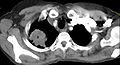

-

CT scan showing a Pancoast tumor (labeled as P, non-small cell lung carcinoma, left lung), from a 47-year-old female smoker